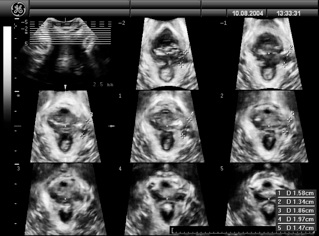

Another way is via 3D/ 4D (tomographic) ultrasound which allows an assessment of pelvic floor trauma such as levator avulsion injuries and hiatal ballooning. (The width and depth of defects are able to be measured or estimated, and the number of abnormal slices correlating with the likelihood of prolapse and symptoms of prolapse are assessed). (2)

Taken from Professor Peter Dietz site